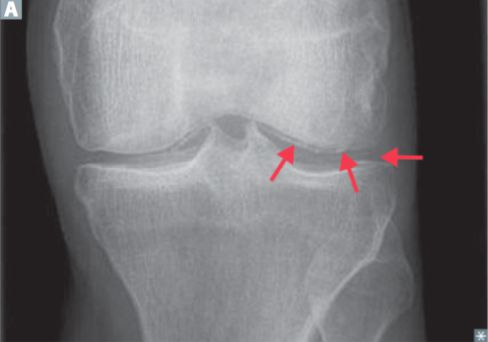

- X-ray of the affected joint(s)

- Chondrocalcinosis: calcification of cartilage in the affected joints